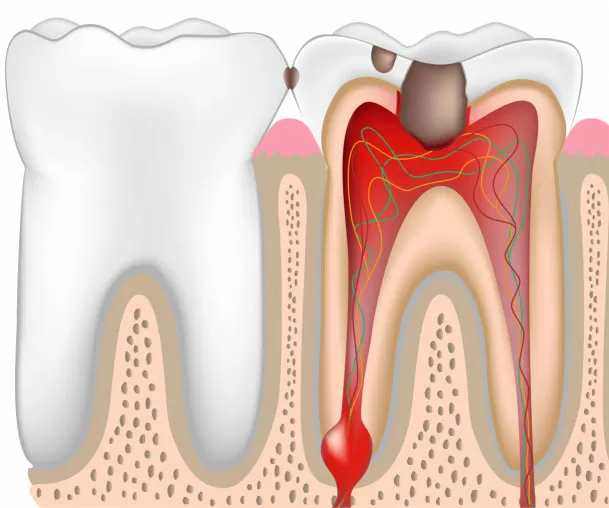

Болезни зубов

В разделе описаны все известные поражения зубов в коронковой части (эмаль, дентин, шейка и пульпа), заболевания пульпы, корня, периодонта и альвеолы. В статьях собрана информация о симптомах, причинах, лечении (профессиональном и народном в домашних условиях) и профилактике любой зубной беды. Рекомендуем не заниматься самодиагностикой и тем более самолечением! Помните, что запущенные проблемы с зубами всегда поражают десны, об этом читайте в соседнем разделе Заболевания десен.